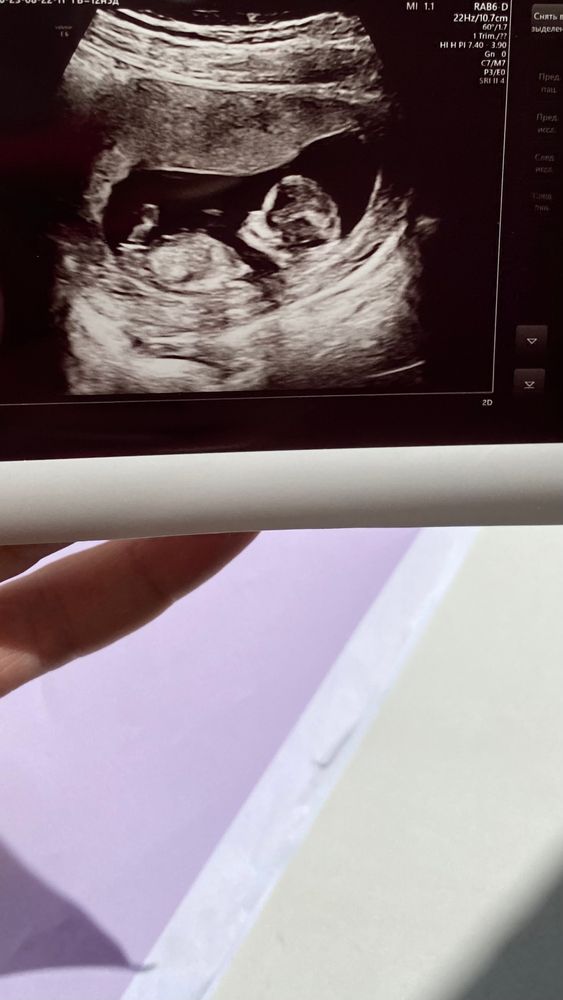

Судя по положению полового бугорка, у вас девочка

Девочка.

У девочек писюн более параллельно, будто часть пельмешки.

У мальчиков торчит дальше от тела.

Если это половой бугорок, то девочка, от почти параллелен телу, прям как на картинке в учебнике🥰 но я не узист, просто любитель 🤣🤣🤣

На мальчика похоже, как будто семенные канатики вижу. Вы уже знаете ответ ?